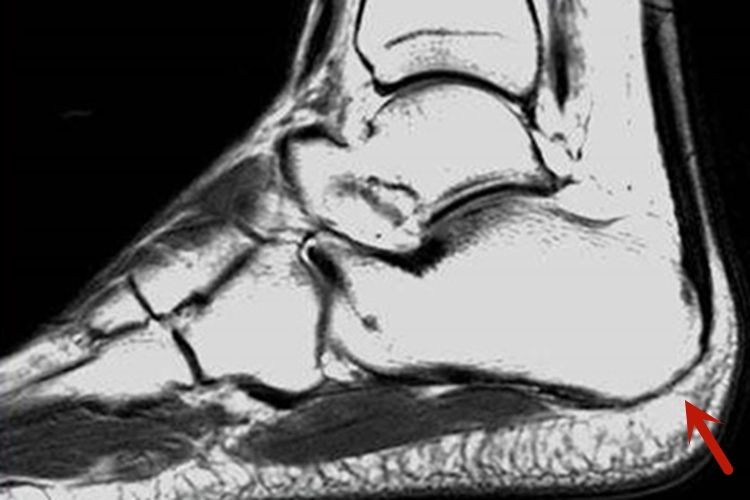

在磁共振检查下可见跟骨整体近似长方形,后方跟骨体的后面呈卵圆形隆起,整体以骨松质为主,所以可见高低混合的信号影。